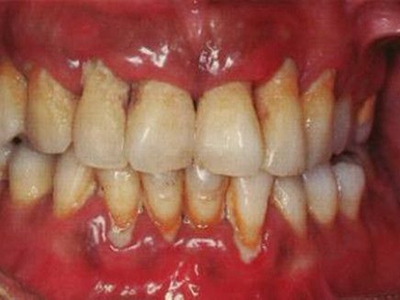

慢性龈炎的病损部位一般局限于游离龈和龈乳头,以前牙区为主,尤其以下前牙区最为显著,患者常因刷牙或咬硬物时牙龈出血而就诊。游离龈和龈乳头颜色变为鲜红或暗红色,病变较重时炎性充血可波及附着龈。龈缘变厚,龈乳头圆钝肥大,可增生呈球状,覆盖牙面。牙龈松软脆弱,缺乏弹性。

当牙龈以增生性反应为主时,龈缘和龈乳头呈坚韧的实质性肥大,质地较硬而有弹性。龈沟液量增多,还可能出现龈沟溢脓现象。

龈缘附近牙面上堆积的牙菌斑是引起慢性龈炎的始动因子,其他如牙石、食物嵌塞、不良修复体等均可促使牙菌斑积聚,引发或加重牙龈炎症。